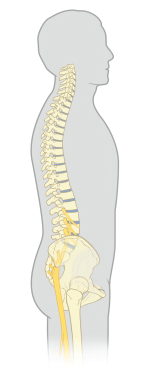

Now that your surgery is complete, you should start working on standing up straight again for improved posture and to reduce pressure on your spine. It may feel awkward and/or uncomfortable at first.